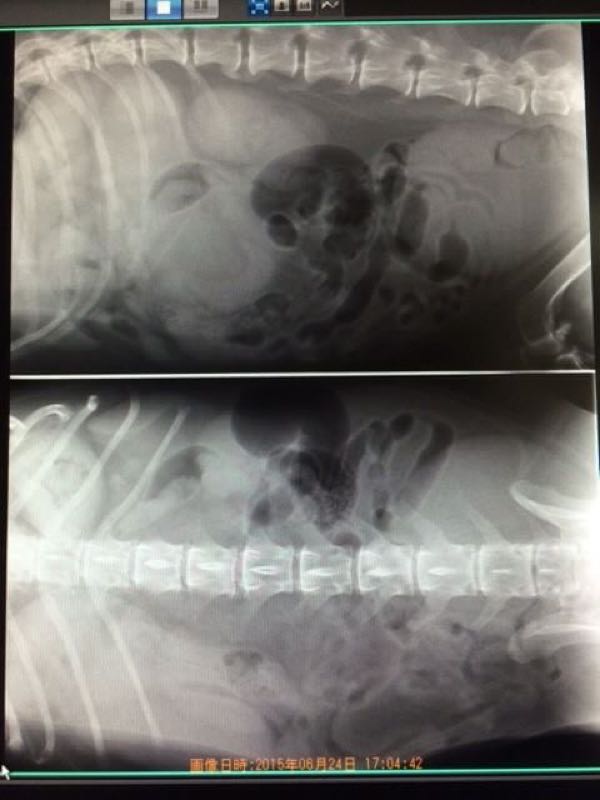

最初の問診で、ブンブンの様子を見た先生は

麻酔なしでCT撮りましょう

と言ってくれました。

手術するのなら、麻酔を打って、精密なCTが必要ですが、 できるかどうかを診ることと、他の臓器への転移を見るくらいなら、少し固定させてもらえたら、息まで止めなくても大丈夫でしょう

結果、大静脈と接触しているけれど、巻きついたり、食い込んだりはしていない。

箇所が、背中に一番近い所なので、仰向けに寝かせると、一番奥の手術になります。

時間は3、4時間くらいです。

今の所、胃腸、膀胱を圧迫していることもありません。

直径10センチほどもあり、大きいのですが、他の臓器への転移は見られないので、もしかしたら悪性ではないかもしれません。